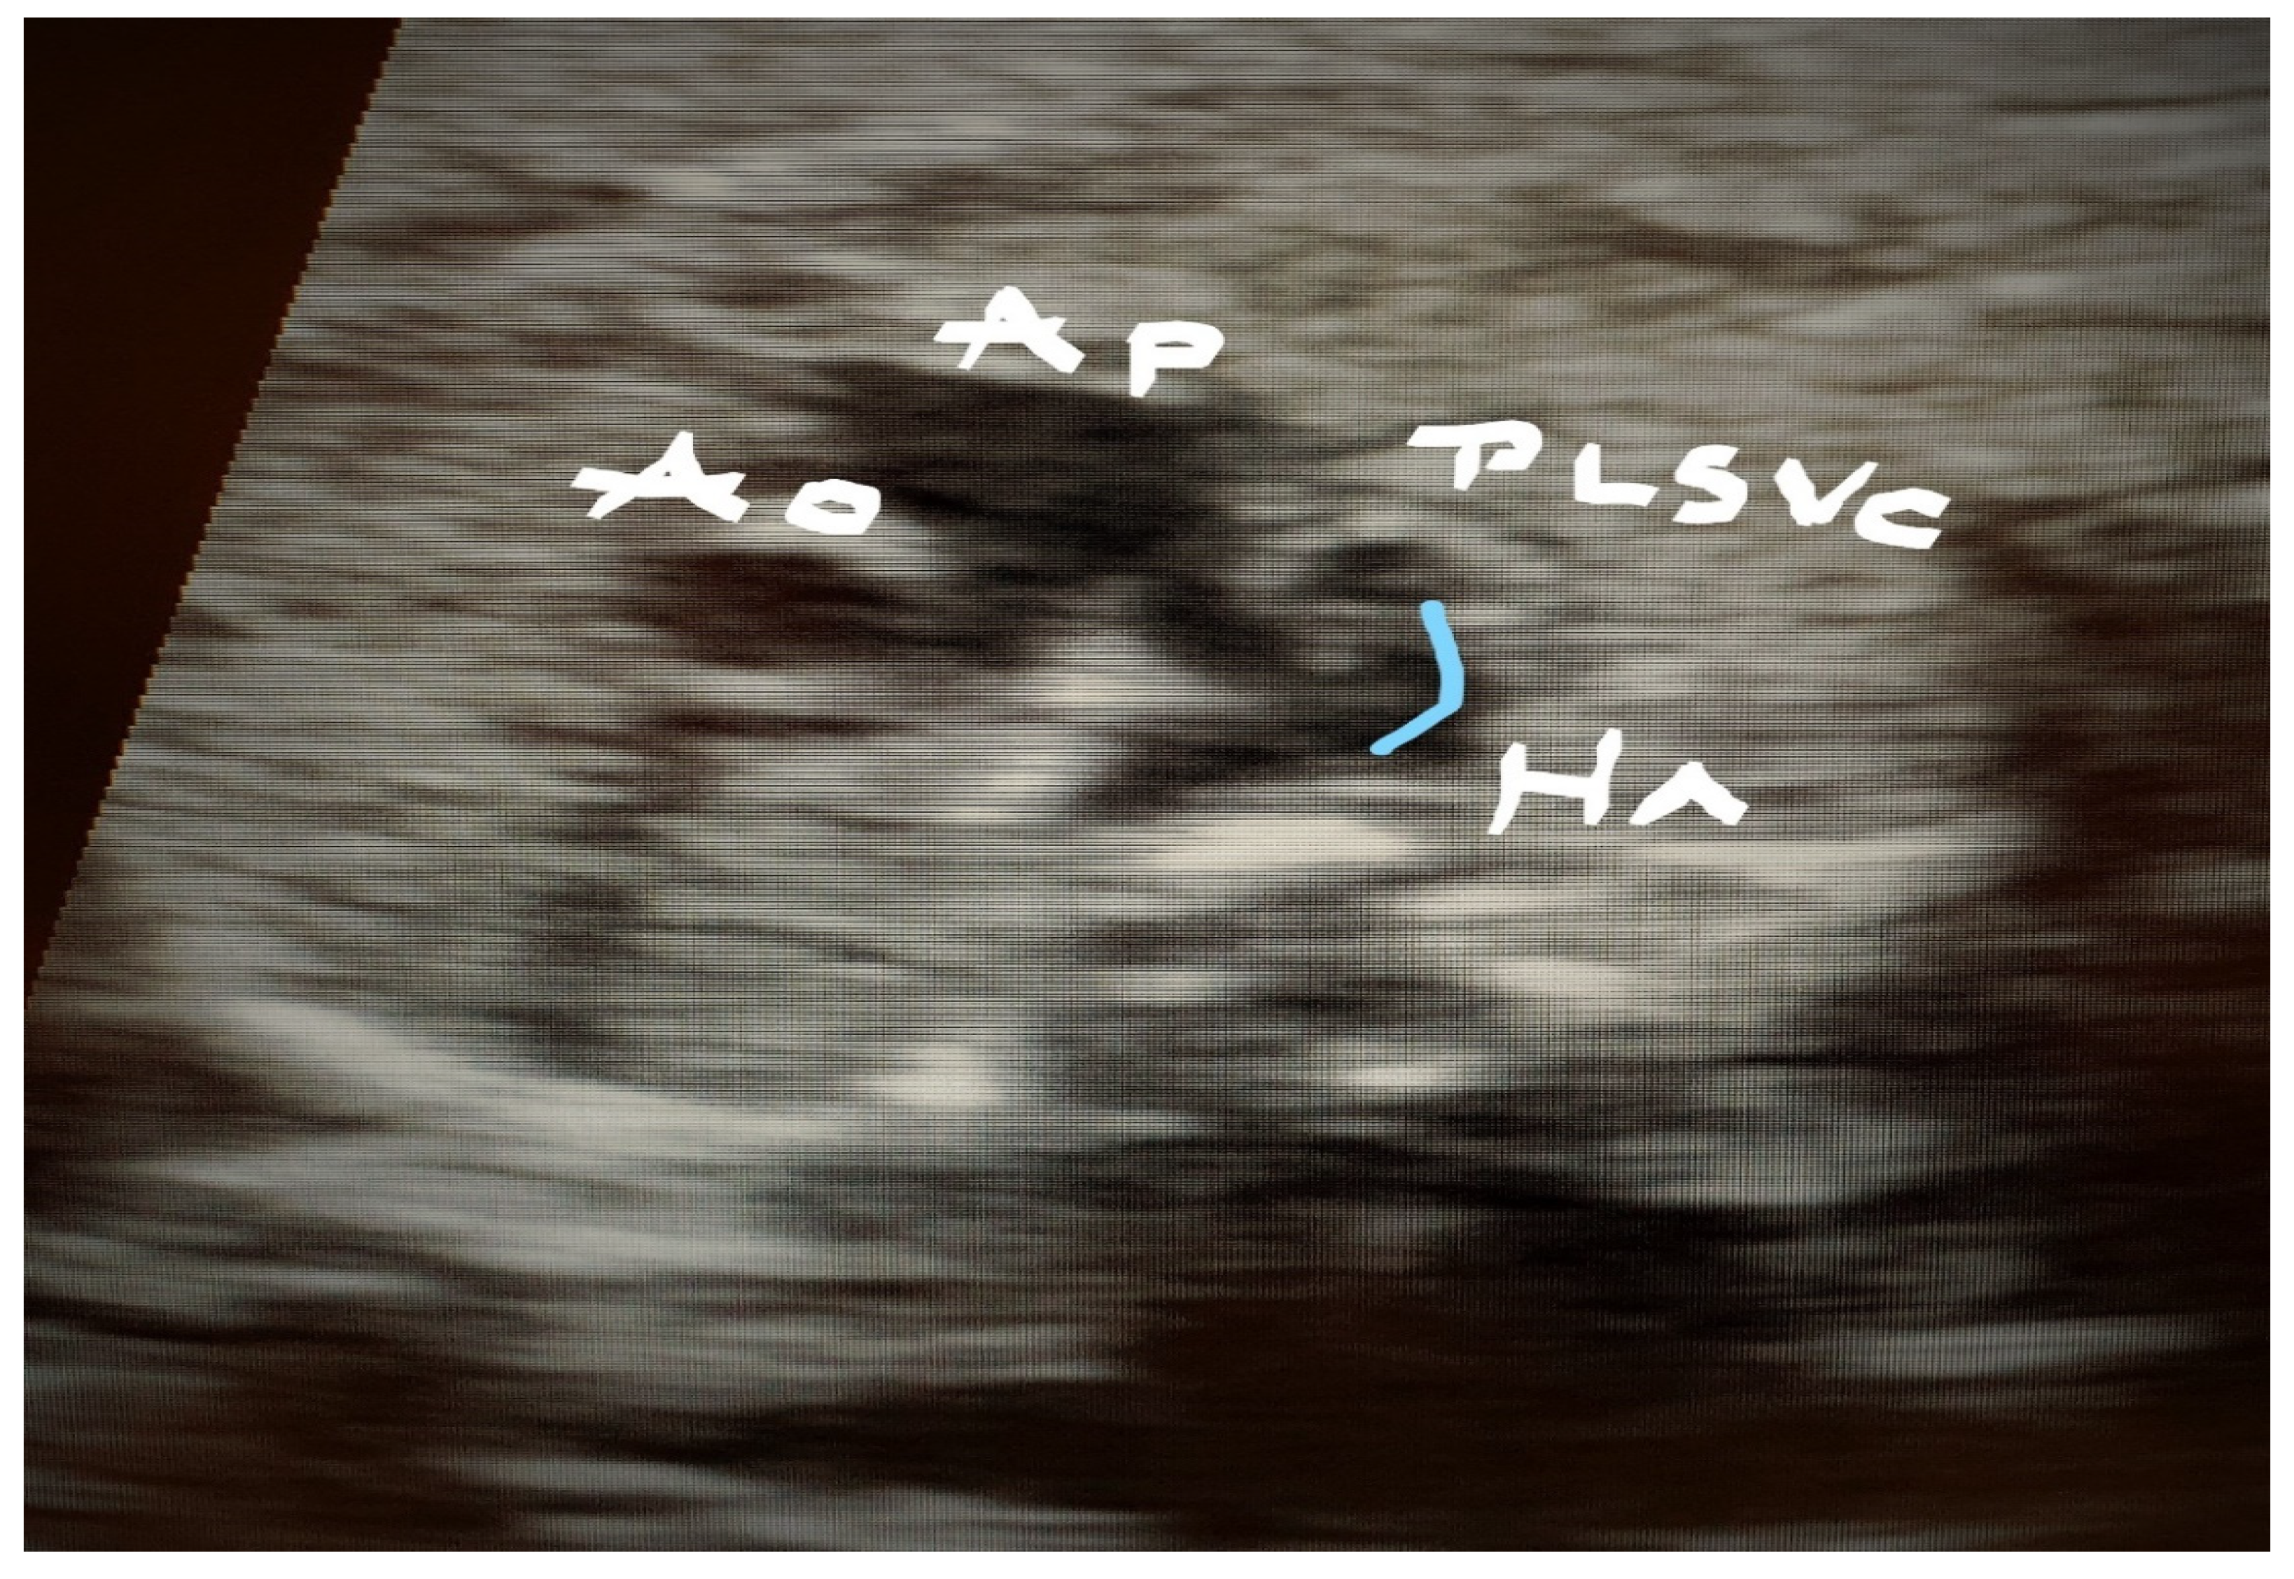

4. Cases—Ultrasound Findings Description

4.1. Case 1

4.2. Case 2

4.3. Case 3

4.4. Case 4